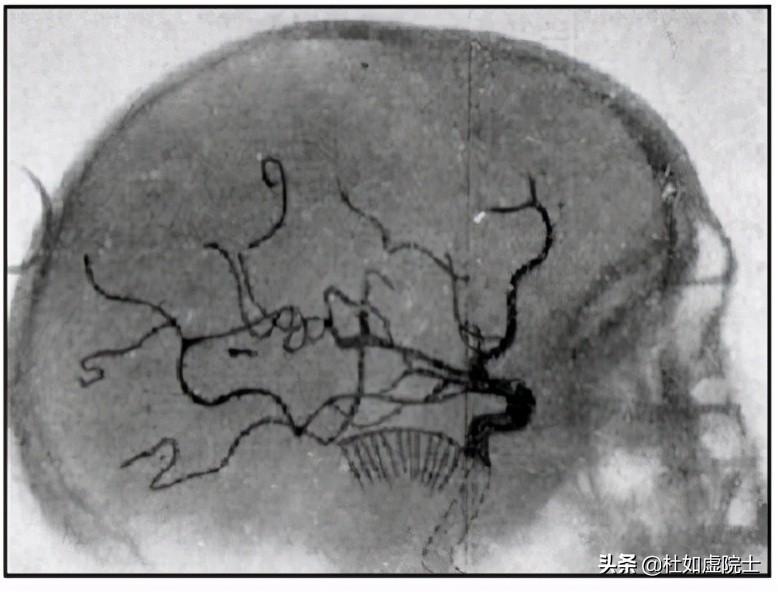

1927年,葡萄牙醫(yī)生安東尼奧·伊加斯·莫尼茲(Antonio Egas Moniz,1874—1955)發(fā)明了用X射線觀測腦血管的血管造影技術(shù)。莫尼茲是個特殊人物。1902年,他獲得醫(yī)學(xué)博士學(xué)位后不但行醫(yī),而且從政,曾任葡萄牙的外交部長。1926年,他離開了政界,到里斯本大學(xué)任神經(jīng)科教授。翌年,他開發(fā)出了血管造影的技術(shù)(圖6)。這一技術(shù)的關(guān)鍵是在動脈注入顯影劑,當(dāng)顯影劑隨血液流過大腦時用X光進行分析。1936年,他又發(fā)明了用前額葉皮層切除術(shù)(Prefrontal leucotomy)調(diào)節(jié)大腦神經(jīng)的病變,卻導(dǎo)致了一些病人終身不能自理。其中的是約翰·肯尼迪(John F. Kennedy, 1917—1963)的妹妹Rosemary Kennedy。1949年,莫尼茲獲得了諾貝爾醫(yī)學(xué)獎。同年他被他的一個病人開槍打傷,只能坐在輪椅上。過了幾年就逝世了。莫尼茲還是作家,寫過好幾本關(guān)于葡萄牙歷史人物的書籍,流傳至今。

圖6,安東尼奧·伊加斯·莫尼茲及他的血管造影術(shù)